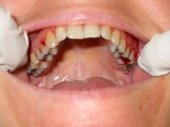

Alteraciones de los tejidos parodontales (encía, ligamento y hueso) por problemas funcionales |

Sangrado gingival espontáneo, infecciones

en las encías o movilidad dentaria debidos al desequilibrio oclusal